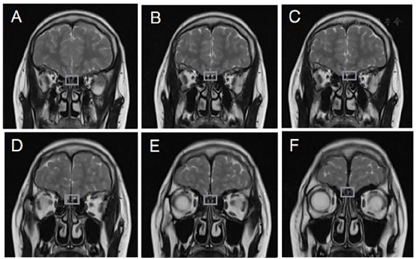

心电图提示窦性心律不齐。胸片提示心肺未见明显异常。骨龄片提示相当于16~17岁左右(图1)。第2~4腰椎椎体骨密度值减低(全部Z值-4.5,最低-5.3),提示骨质疏松;左髋关节、大转子密度值在正常范围(全部Z值-0.5,最低-1.5)。心脏彩超:心脏结构及功能未见明显异常。乳腺彩超提示男性乳腺未见明显占位性病变。阴囊彩超提示双侧睾丸体积偏小(切面内径左侧约14.2 mm×6 mm×9.9 mm,右侧约15 mm×5.9 mm×10.9 mm)。全腹彩超:前列腺体积稍小(大小约14 mm×10 mm×13 mm)。肝、胆、胰腺及腹膜后所见部位、脾、双肾、双输尿管、膀胱未见明显占位性病变。腹主动脉所见部位未见明显异常。垂体+嗅球、嗅束磁共振:垂体MRI平扫及增强未见明显异常;双侧嗅沟存在、显示稍小,双侧嗅球、嗅束未见显示(图2)。

注:方框显示嗅沟、嗅球、嗅束位置,提示双侧嗅沟存在、但稍小,双侧嗅球、嗅束未见显示